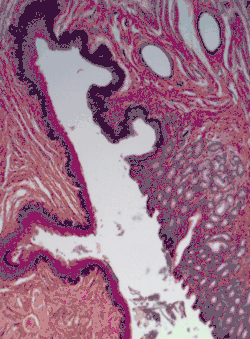

![]() | |

![]() Section of the human skin showing the stratified squamous epithelial surface, referred to as the epidermis. The layer of keratin here is named the stratum corneum. | |

In the epidermis of skin in mammals, reptiles, and birds, the layer of keratin in the outer layer of the stratified squamous epithelial surface is named the stratum corneum. Stratum corneum is made up of squamous cells which are keratinized and dead. These are shed periodically.